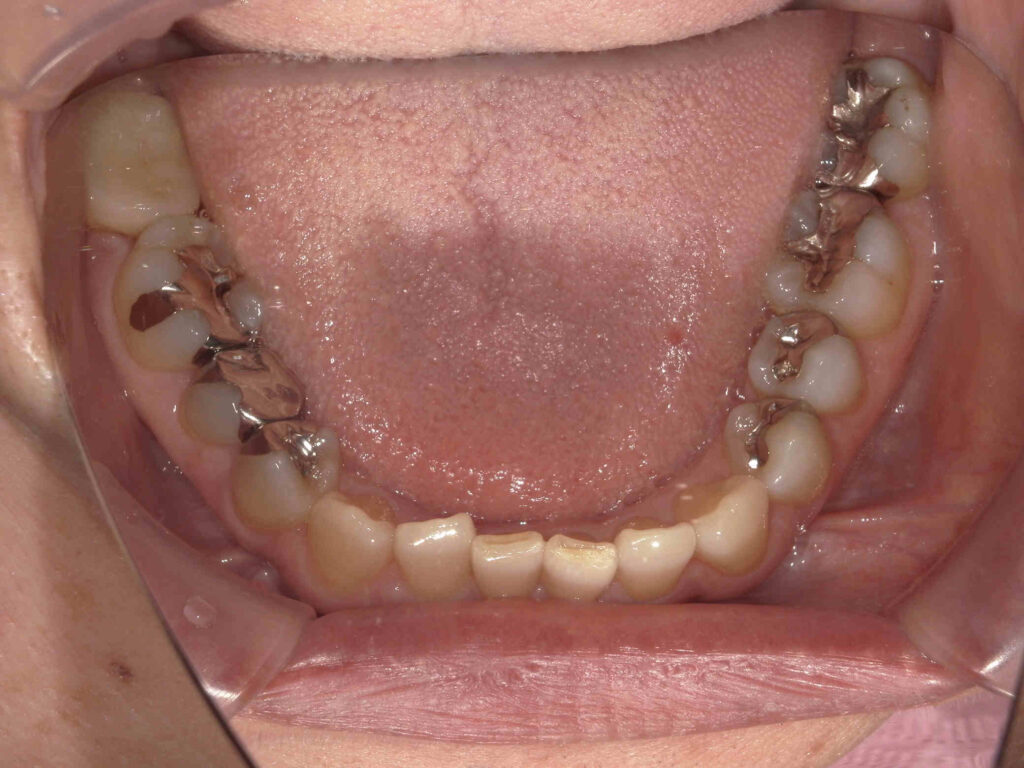

BEFORE

銀歯が目立ちます

| 主訴 | 銀歯をなくしたい |

|---|---|

| 診断名・ 主な症状 |

メタルインレーによる審美障害 |

| 年齢 | 50代女性 |

| 治療内容 | グラデーションジルコニアインレー修復 |

| 治療期間/ 通院回数 |

2カ月/4回 |

| 費用 | 616,000円 |